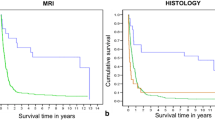

Childhood brain tumors show great histological variability. The goal of this retrospective study was to assess the diagnostic accuracy of multimodal MR imaging (diffusion, perfusion, MR spectroscopy) in the distinction of pediatric brain tumor grades and types. Seventy-six patients (range 1 month to 18 years) with brain tumors underwent multimodal MR imaging. Tumors were categorized by grade (I–IV) and by histological type (A–H). Multivariate statistical analysis was performed to evaluate the diagnostic accuracy of single and combined MR modalities, and of single imaging parameters to distinguish the different groups. The highest diagnostic accuracy for tumor grading was obtained with diffusion–perfusion (73.24 %) and for tumor typing with diffusion–perfusion–MR spectroscopy (55.76 %). The best diagnostic accuracy was obtained for tumor grading in I and IV and for tumor typing in embryonal tumor and pilocytic astrocytoma. Poor accuracy was seen in other grades and types. ADC and rADC were the best parameters for tumor grading and typing followed by choline level with an intermediate echo time, CBV for grading and Tmax for typing. Multiparametric MR imaging can be accurate in determining tumor grades (primarily grades I and IV) and types (mainly pilocytic astrocytomas and embryonal tumors) in children.